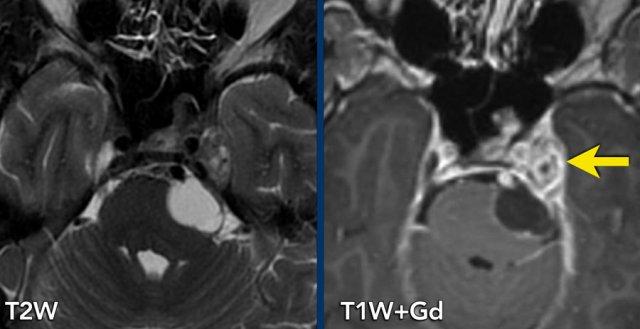

Các hình ảnh này thuộc về bệnh nhân nam 49 tuổi với biểu hiện rối loạn cảm giác nửa mặt trái và cảm giác tức nặng sau mắt trái.

Chuỗi xung T2W cắt ngang cho thấy một tổn thương tại hang Meckel và đoạn bể dịch não tủy của dây thần kinh sinh ba. Thành phần trong hang Meckel có cấu trúc đặc và ngấm thuốc tương phản từ đồng nhất trên ảnh T1W sau tiêm (mũi tên).

Thành phần trong bể góc cầu tiểu não gần như hoàn toàn dạng nang và chỉ ngấm thuốc ở vỏ nang.

Tổn thương được chẩn đoán là u schwannoma thần kinh sinh ba.

Sự phát triển của tổn thương dọc theo thần kinh, gây thắt hẹp tại lối vào hang Meckel, tạo nên hình ảnh kinh điển dạng “quả tạ” (dumbbell shape).